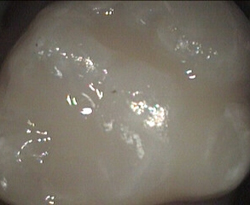

Unusual prevalent but superficial groove pattern on permenant molar after Sealed

unusual wide but superficial decay after